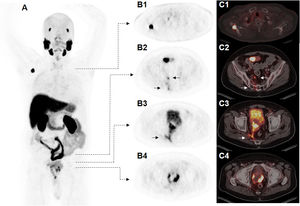

The contrast enhanced mpMRI demonstrated a locally advanced prostate cancer with infiltration of mesorectal fascia, right seminal vesicle and, besides, oedema with contrast enhancement of the right piriformis muscle and thickening of the nerval roots of the plexus sacralis indicated tumor infiltration, albeit mpMRI has limitations for the correct identification of mucinous parts of prostate carcinoma. In addition, mpMRI revealed multiple lymph node metastases in the pelvis. Despite morphologically extensive tumor involvement of the pelvic organs and the known diagnostic superiority of mpMRI over PET/CT regarding the soft tissue evaluation, a contrast-enhanced, whole-body [18F]PSMA-1007 PET/CT scan had to follow for a better tumor delineation in the area of sacral plexus, as this plays a pivotal role for the quality of life for patients as well as a correct radiotherapy planning (determination of gross tumor volume = GTV). The PSMA imaging revealed a locally advanced prostate cancer with infiltration of adjacent structures and organs involving right seminal vesicle, reaching to the anterior wall of the rectum and metastasis to pelvic lymph nodes and a further solitary metastasis to right scapular bone (Fig. 1). The tumor findings in the pelvis exhibited in total a moderate PSMA uptake with an SUVmax of up to 18.1, whereas the metastases to lymph nodes showed rather low PSMA uptake with an SUVmax of up to 1.9. An intensive [18F]PSMA-1007 uptake was seen in the scapular bone with an SUVmax of up 34.0 with no CT correlate. Clinically most significant [18F]PSMA-1007 finding was the identification and also correct tumor delineation in the area of sacral plexus, as [18F]PSMA-1007 imaging here adds further information to the MRI findings (Fig. 2).2,3 In the following clinical course, the patient received a PSMA-guided, palliative radiotherapy of the pelvic parts of malignant spread in combination of a systemic androgen deprivation therapy (ADT). The scapular lesion underwent osteoblastic changes after the initiation of ADT, which was interpreted as a validation of malignancy.

[18F]PSMA-1007 PET/CT scan; Maximum intensity Projection (MIP) (A), PET imaging (B1 − 4), fused [18F]PSMA-1007 PET/CT images (C1 − 4). Solitary metastasis of the right scapular bone (B1 and C1). Lymph node metastases and infiltration of the sacral foramina (B2 + C2) and the right piriformis muscle (B3 + C3). Intraprostatic PSMA uptake and central hypodense extension after multiple transurethral resections (B4 + C4).